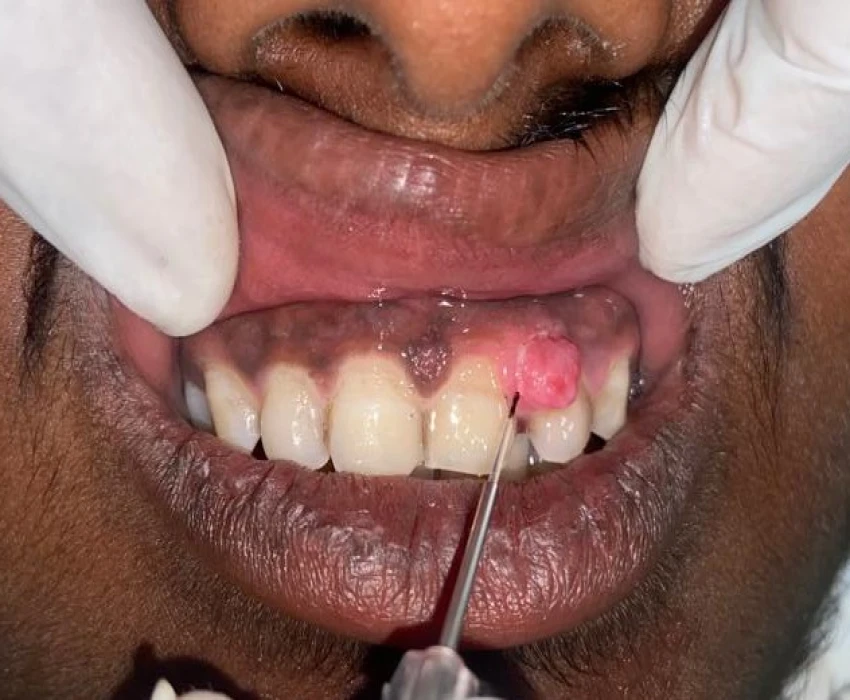

A 19 years old male patient reported to the Department of Oral Medicine and Radiology with a chief complaint of growth in left upper front region of jaw since 2 years. It was diagnosed as Pyogenic Granuloma i.r.t. 22 and differential diagnosis of Peripheral Ossifying Fibroma was given and the final diagnosis came out to be as Peripheral Cemento-ossifying Fibroma as per histopathological analysis.

LASER excision of the lesion was done.